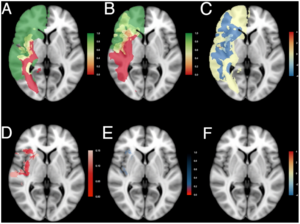

- 7.20 Brain Regional Lesion Burden and Impaired Mobility in the Elderly